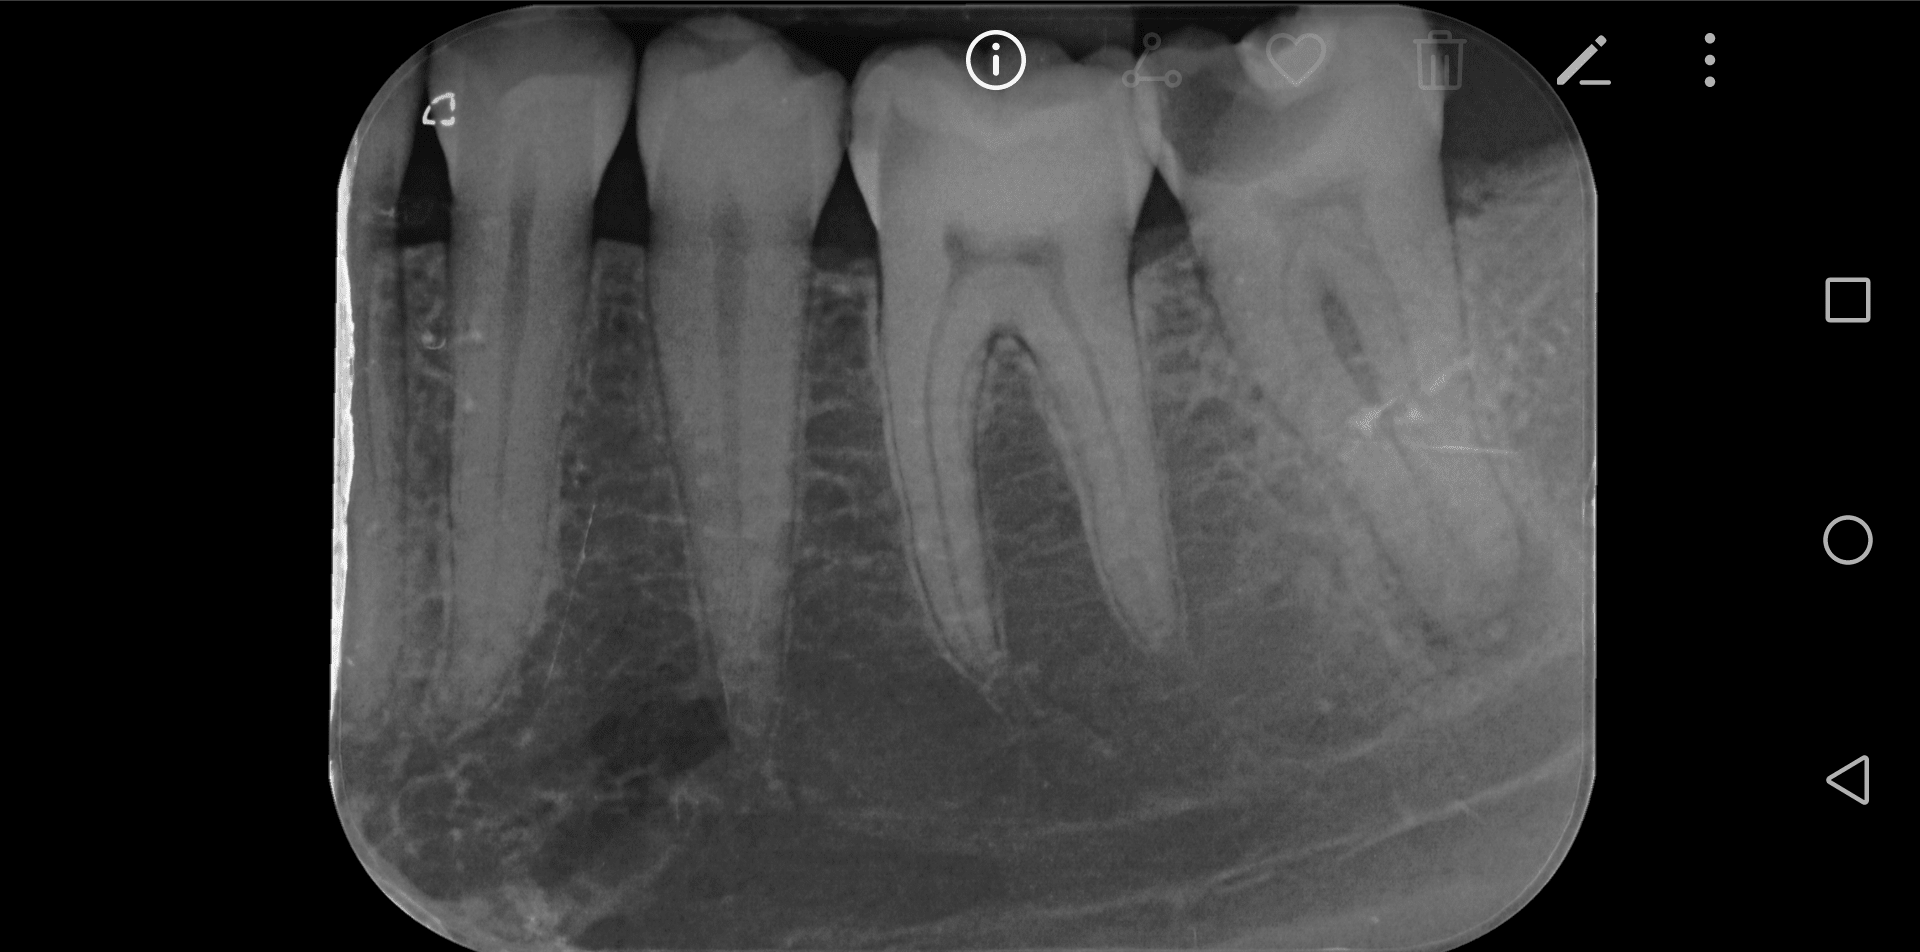

Diagnostic : Parodontite chronique apicale en phase aigue, il y a une semaine. Anesthesie impossible à ce moment la, mise sous AB depuis 5 jours. Au vu de la radio pre-op je considère le TR comme potentiellement compliqué.

Un gros canal Distal très excentré en vestibulaire est trouvé, ainsi qu'un fin canal MV relié au canal distal par un isthme peu profond. Je trouve également un fin canal ML. Les deux canaux mésiaux se situent bien en mesial, sur la même ligne parallèle au bord mesial et séparés de 1mm.

merci pour vos réponses, Pour la perf, je ne pense pas… D'ailleurs sur la pré-op on semble voir quelque chose à l'endroit de ma future pseudo perf..?

Si je regarde le plancher de la chambre pulpaire (couple transversale), mon C est relativement peu bombé en forme et va du MV classique au distal excentré en vestibulaire. Le dos du C est vers vestibulaire. N'es-ce pas curieux au vu de la radio pre-op ou l'on voit deux racines mesiale et distal séparées ? Ou bien le C est vraiment très peu profond comme j'en ai l'impression.

Bon après lecture des réponses et réflexion, j'opte (j'espère); soit, le moins probable, pour un canal secondaire de la chambre vers l'espace inter radiculaire, soit, le plus probable pour une anatomie en C donnant l'impression que mon MV est en inter radiculaire (type TIB postée par BURNAX).

Je vais tabler sur une morphologie en c (5 à 7% des 2e molaires mandibulaires) et une imagerie à la "burnax". Le plancher pulpaire ressemble au cas posté par Bill. Un c vestibulaire de distal à mv et un canal individualisé en ml. Dans ce cas le mv peut apparaître dans la furcation à la radio...